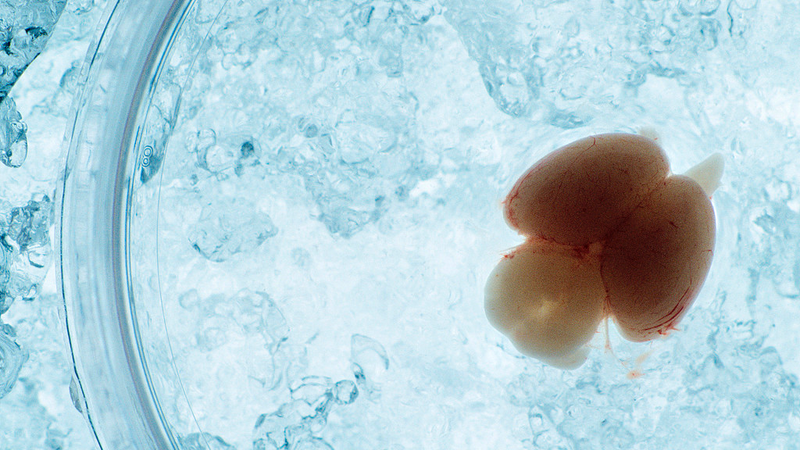

胎内にいる胚の脳が、どの瞬間にどう形づくられていくのか——。中国の研究チームが、胚マウスの脳発達を「生きたまま」長時間追える胎内イメージング技術を開発し、神経発達の動きをより具体的に捉えたと報じられました。

Science and Technology Dailyによると、清華大学の研究チームが「胚マウス胎内(子宮内)でのin vivo観察」を可能にする撮像手法を開発しました。研究成果は、このほど学術誌Cellに掲載されたとされています。

論文の責任著者であるMi Da氏によれば、新手法は二光子顕微鏡(深い組織を比較的観察しやすい顕微鏡手法)をベースに、胚マウスを固定・安定化する補助支持デバイスを組み合わせています。これにより、胎内でのライブ観察を「長時間・広視野・深部組織」まで広げたといいます。